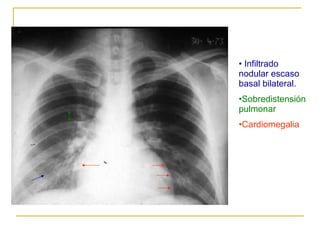

Infiltrado nodular escaso basal bilateral. Sobredistensión pulmonar Cardiomegalia

Infiltrado basal bilateral. Sobredistensión pulmonar Cardiomegalia